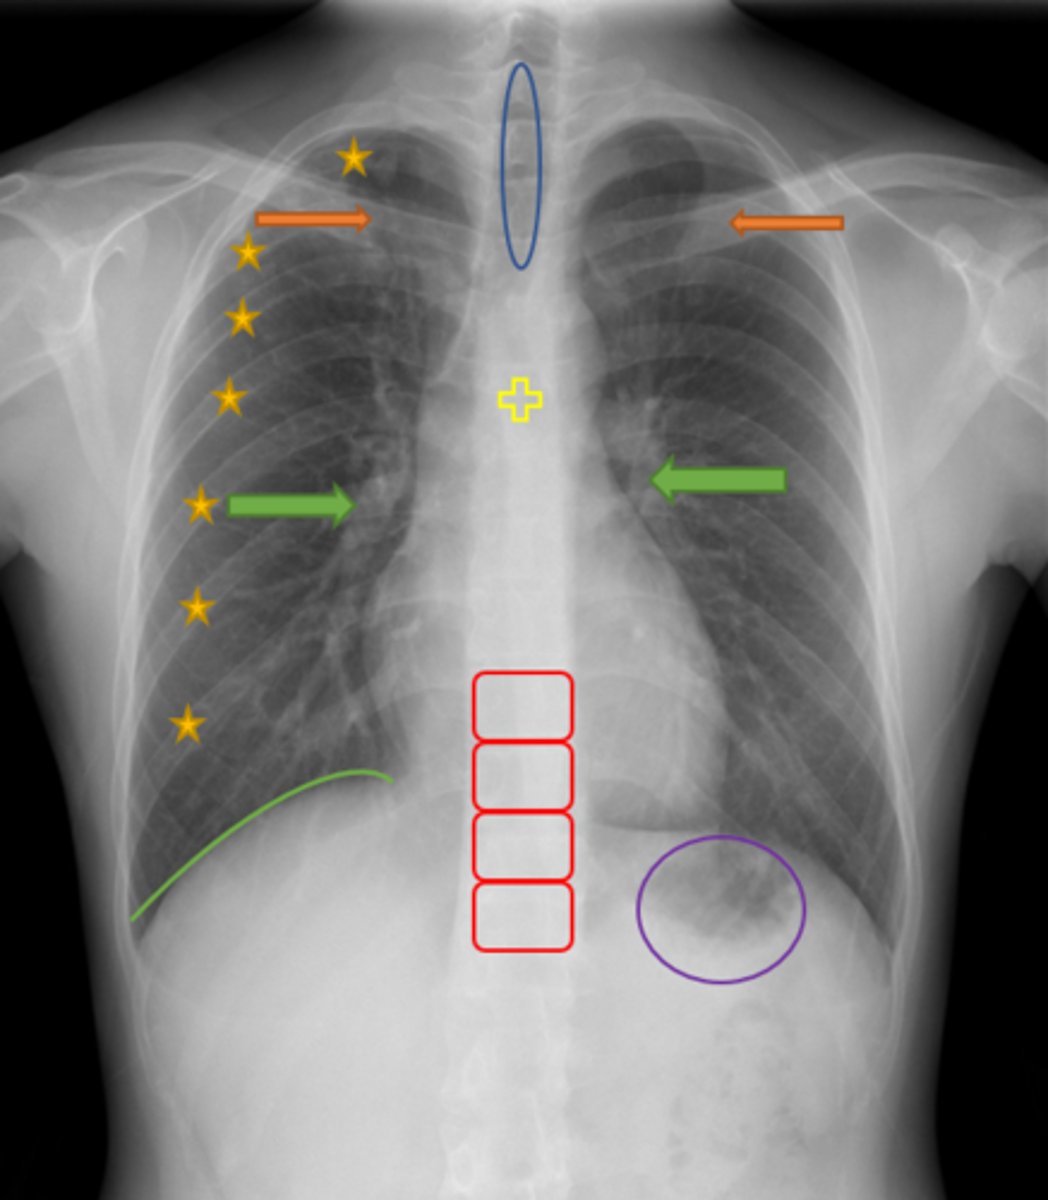

Aortic knob/arch

Pink Arrow

Left ventricle and border of the heart

Purple Line

Pulmonary arteries

Blue Arrows

Trachea

Blue Oval

Green Arrows

Vertebrae/spine

Red Blocks

Clavicle

Orange Arrows

Ribs

Yellow Stars

Diaphragm

Green Line

Gastric bubble/stomach

Purple Circle

Carina

Yellow Cross